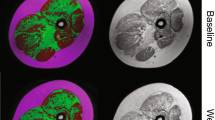

Multipolar gradient echo (GE) images were acquired at 3 different echo times (TR/TE = 430/8.06, 9.21, 10.36 ms) over 25 axial slices (4 mm slice thickness, 1 mm gap) with a 20° flip angle using mDixon (Philips) and field of view adjusted depending on subject anatomy [19]. Experienced image analyzers selected slices based on a standardized anatomical landmark, and outlined the BB, TB, DEL, subscapularis (SUB), infraspinatus (INF) posterior compartment of the forearm (PF), and anterior compartment of the forearm (AF). Regions of interest (ROIs) were traced on the water map and applied to the FF map (Fig. 2). For each muscle, analyzers took care to avoid inclusion of extramuscular tissue such as bone, subcutaneous fat, or other muscles in the outlined segment. Three consecutive slices in or near the muscle belly were analyzed for each muscle, and the pixel-by-pixel FF values were averaged to give a mean FF for each muscle.

MRI-T2 maps were generated by acquiring T 2-weighted images with a TR of 2000 ms and 5 TE’s evenly spaced from 20 to 100 ms. The signal intensity in each pixel was fit to a single exponential decay to compute pixel-by-pixel T2 maps (Fig. 2). The first TE was excluded from analysis to reduce the bias from stimulated echoes [2, 9, 21]. ROIs were traced on the first TE image and applied to the T2 map in a similar manner to the MRI-FF ROIs. Three consecutive slices were analyzed for each muscle, and the pixel-by-pixel T 2 values were averaged to give a mean T 2 for each muscle.

Each subject tolerated the positioning and duration of the scanning procedures well. Representative images and spectra acquired from the upper extremity musculature in unaffected CON subjects and boys with DMD are shown in Figs. 3 and 6. MR biomarkers, specifically MRI T2 (Figs. 4, 5) and 1H20 T2 (Table 1), in the upper arm differentiated CON and DMD subjects (p < 0.05). A comparison across muscles showed the highest T 2 values in the shoulder muscles, followed by the upper arm, and forearm muscles (Figs. 4, 5).

MR-derived FF images demonstrated muscle deterioration in the proximal upper extremity muscles in boys aged 11–16 years. The increase in fat fraction measured using chemical shift-encoded imaging in the upper arm muscles was confirmed using MR spectroscopy of the BB (Table 1; Fig. 6a, b). FF measures determined by chemical shift-encoded imaging showed a strong correlation with MRI-T2 measures (r = 0.75; Fig. 6c), confirming a predictable relationship between these measures.